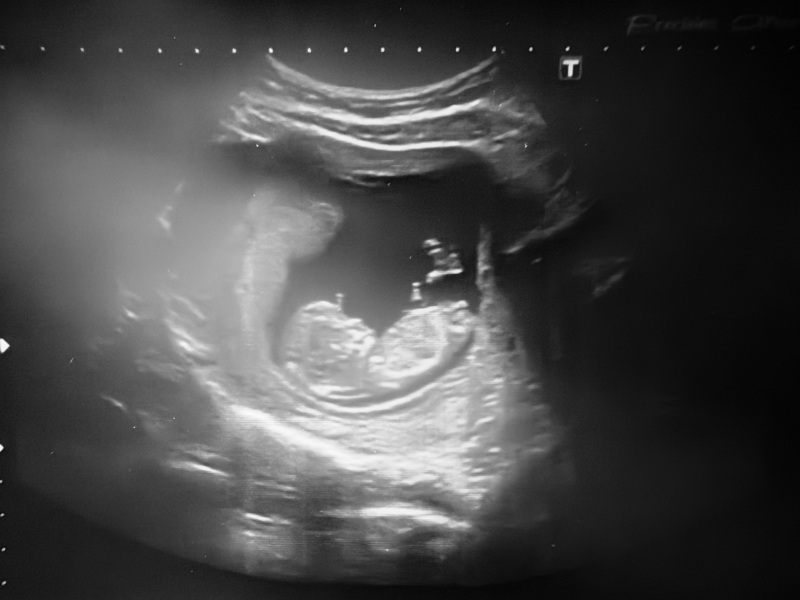

Any guesses on baby's sex from my pregnancy scan?

Any guesses of the gender? Facebook groups are 50/50 🤷🏽‍♀️

A boy 💙 congratulations! I’ve never been wrong yet.